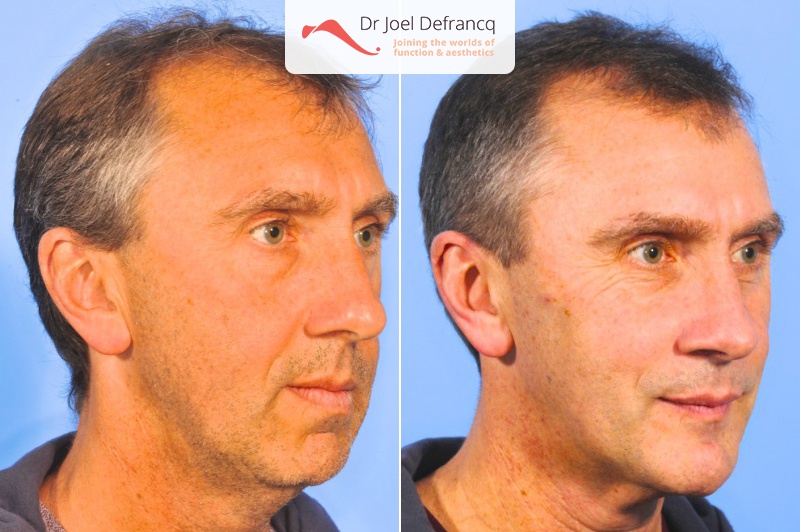

Kaakchirurgie

- Verlenging onderkaak (BSSO)

- Verlenging bovenkaak (Le Fort I)

- Rotatie bovenkaak

- Onderkaak rotatie

- Kinchirurgie

Behandeling tandheelkundige implantaten

- Vaste tanden op implantaten (bovenkaak)